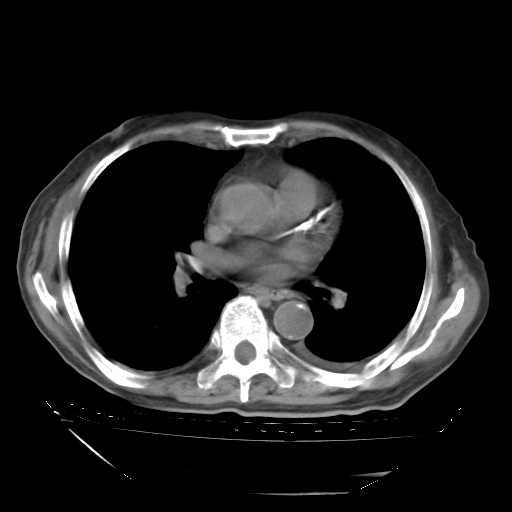

经过24天治疗,岳父的病情基本稳定。生活基本可以自理,可以下床活动。呼吸困难早已消失。体温基本正常。

只是甲强龙用80mg时血小板升到正常,改为60mg后又降到63×10*9/L。

主要治疗甲强龙80mg×14天,60mg×10天;同时抗结核(异烟肼+利福平+乙胺丁醇)。环磷酰胺0.1 tid 10天。

特别感谢胡教授、高管、桃子版主给出关键的治疗建议。桃版把所有肺部影像和全部临床资料请所在医院呼吸科、感染病科、结核科、临床免疫科专家会诊。临床免疫科专家制定了完整的治疗方案。